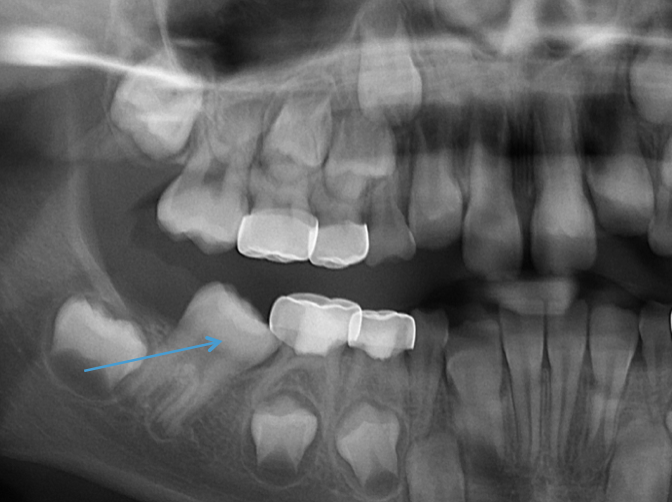

Ectopic Eruption

Ectopically erupting maxillary molar